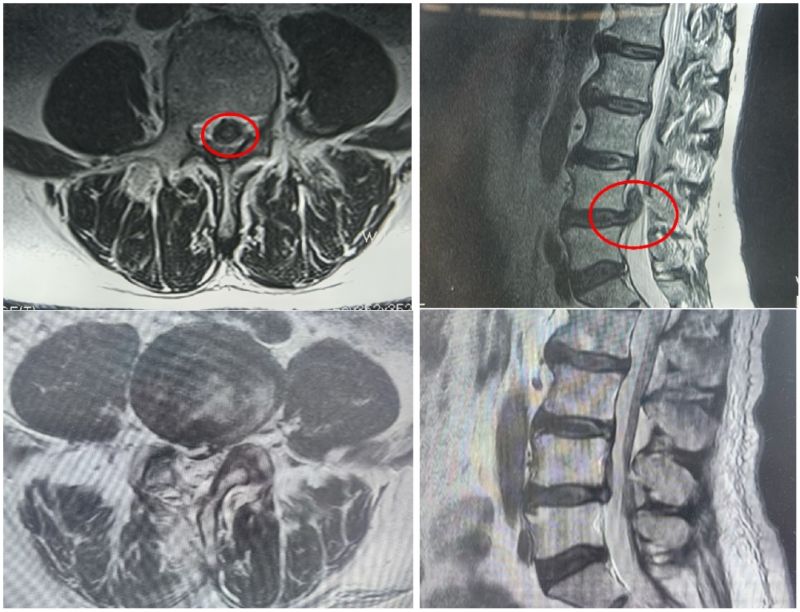

骨科三病区李鹏主任详细询问病情并查体,结合腰椎磁共振,诊断为腰椎间盘突出症伴神经根病。询问病史,患者近1年来饱受疼痛折磨,夜不能寐,到多地医院求医,对开放手术心生恐惧,一直保守治疗。了解病情后,李鹏主任团队制定了UBE微创手术治疗方案,为患者顺利进行了单侧双通道入路内镜下腰4-5椎间盘摘除术、脊髓神经根粘连松解手术。

术前、术后磁共振检查

患者术中出血量不到20毫升,仅留下0.8厘米瘢痕。术后次日杨先生便可下地自由活动,腰腿疼痛感消失,走路也不再一瘸一拐,效果明显,术后5天顺利出院。患者及家人对李鹏主任带领的医护团队表示衷心的感谢。